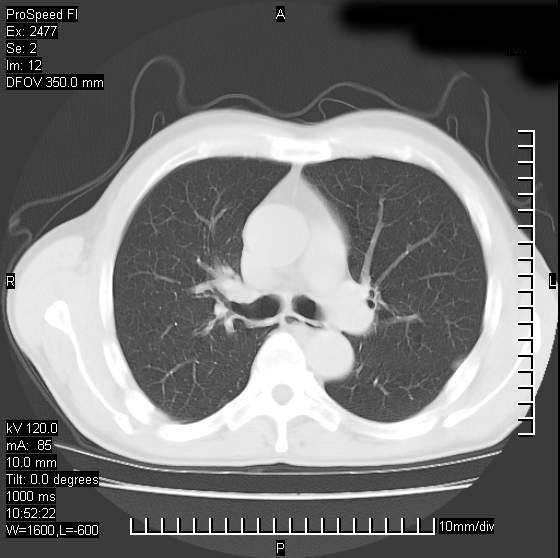

以下是引用天南地北在2007-10-9 14:29:00的发言:[br]1:右上肺结核[br]2:右肺下叶肿块:不支持肺癌,首先考虑炎性病变-肺脓疡可能性大[br]理由:1:临床病史支持,肺脓肿症状不明显应该是不规则服药造成。[br] 2:肿块边缘模糊,周围可见炎性渗出,长毛刺,内见支气管征,不过有点不规则。[br] 我感觉下肺癌这个诊断有点偏左,建议积极抗炎治疗后复查

以下是引用卜一在2007-10-9 15:55:00的发言:[br][br] [br] 1:右上肺结核[br]2:右肺下叶肿块:不支持肺癌,首先考虑炎性病变-肺脓疡可能性大[br]理由:1:临床病史支持,肺脓肿症状不明显应该是不规则服药造成。[br] 2:肿块边缘模糊,周围可见炎性渗出,长毛刺,内见空气支气管征,不过有点不规则。[br] 我感觉下肺癌这个诊断有点偏左,建议积极抗炎治疗后复查![br]支持! [br] [br] [br]

以下是引用wxy7406在2007-10-9 21:02:00的发言:[br]结合临床病史首先考虑感染性病变,但周围型肺癌不能除外,1.患者年龄偏大2.临床有咯血3.(也觉得是最重要的一点)病灶内有偏心性空洞。

以下是引用王仕学在2007-10-9 13:48:00的发言:[br]右下肺周围性肺癌可能性大,最好活检吧

以下是引用hhcckk在2007-10-9 15:18:00的发言:[br]右上肺病灶考虑结核,病灶多种形态并存(纤维化、增殖性病灶并存)[br]右下肺病灶比较难说,个人意见更趋向于“天南地北”的诊断----肺脓肿[br]1、病人有明显的寒战,高热,肿瘤病人很少出现[br]2、病灶周围的肺纹理走向柔和,没有肿瘤病灶常见的集束征[br]3、病灶边缘的毛刺较长,恶性肿瘤多为短毛刺[br]痰中血丝和病人的年龄是两个不利于良性肿块的因素,建议早点活检

以下是引用ydx_74在2007-10-9 15:53:00的发言:[br]右上肺结核,右下中心性肺癌可能大,肺门淋巴结肿大。